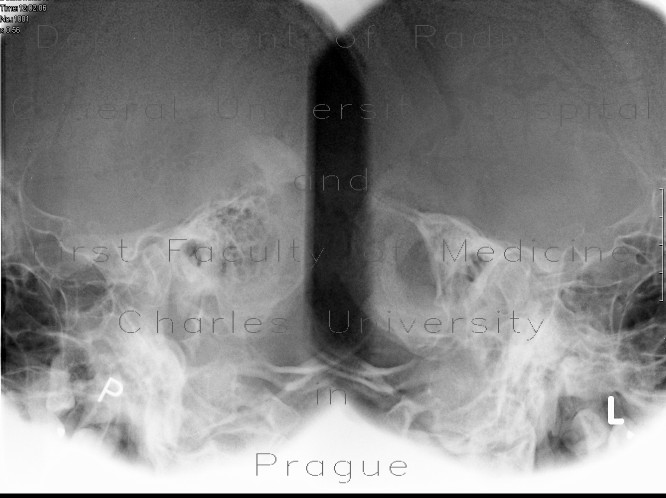

Acute Mastoiditis - Diagnostic Imaging

Bilateral chronic otitis media and mastoiditis with external wall breakthrough and an adjacent subperiosteal inflammatory process or abscess on the left. An immediate left complete corticomastoidectomy for acute suppurative coalescent mastoiditis was performed. ... Return Doc